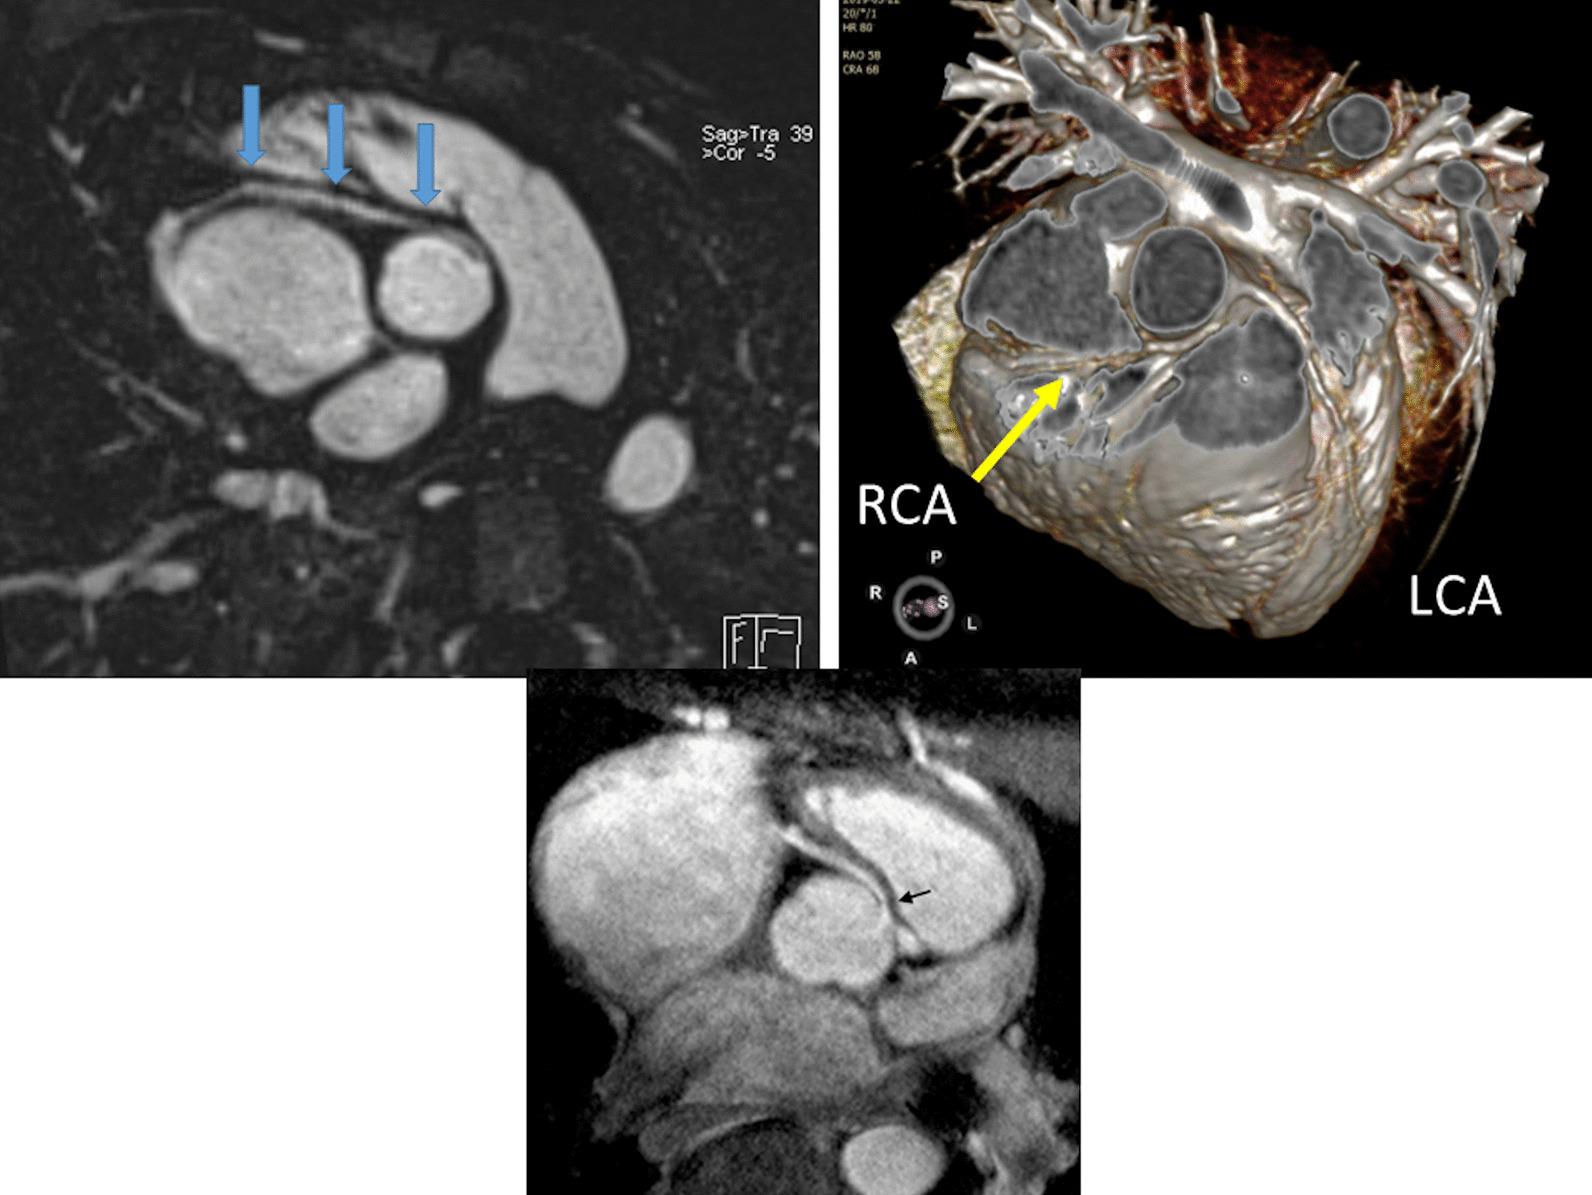

Cardiovascular magnetic resonance (CMR) has been utilized in the management and care of pediatric patients for nearly 40 years. It has evolved to become an invaluable tool in the assessment of the littlest of hearts for diagnosis, pre-interventional management and follow-up care. Although mentioned in a number of consensus and guidelines documents, an up-to-date, large, stand-alone guidance work for the use of CMR in pediatric congenital 36 and acquired 35 heart disease endorsed by numerous Societies involved in the care of these children is lacking. This guidelines document outlines the use of CMR in this patient population for a significant number of heart lesions in this age group and although admittedly, is not an exhaustive treatment, it does deal with an expansive list of many common clinical issues encountered in daily practice.

心血管磁共振(CMR)在儿科患者的管理和护理中已经应用了近 40 年。它已经发展成为评估最小的心脏的宝贵工具,用于诊断、介入前管理和随访。尽管在许多共识和指南文件中提到,但在儿科先天性心脏病和后天性心脏病领域,目前还缺乏一份由众多参与儿童护理的学会共同认可的、最新的、独立的、针对 CMR 使用的大型指南。本指南文件概述了 CMR 在该年龄段的许多心脏病变中的应用,尽管不能说是详尽的治疗方法,但它确实涉及了在日常实践中经常遇到的许多常见临床问题的广泛列表。